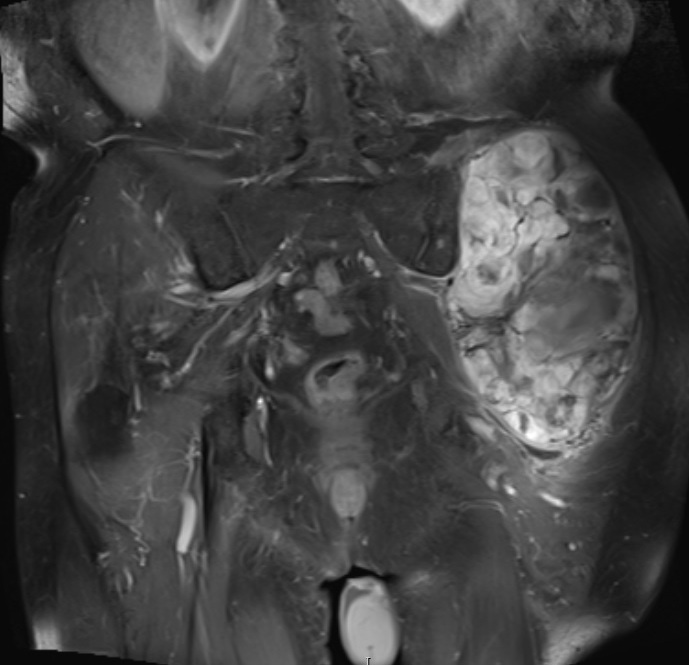

• Large encapsulated lipomatous mass with multiple thick internal trabeculations. (Fig. 1 – 13)

• Signal loss on FS T1 weighted images, and focal nodules(>1 cm is suggestive of a DDLS). (Fig. 1 & 7)

• Contrasted images show hyper-enhancement of the tumors. (Fig. 4, 5, 11-13)

Fig. 1 & 2 Magnetic Resonance Image shows a large heterogeneous mass in the left gluteal region with low intensity signal on Axial (Fig. 1) and Coronal (Fig. 2) T1-weighted images admixed with some high signal areas indicative of fatty tissue. Higher intensity signal is visible compatible with hemorrhage or necrotic tissue. The mass involve the central portion of the left iliac bone.